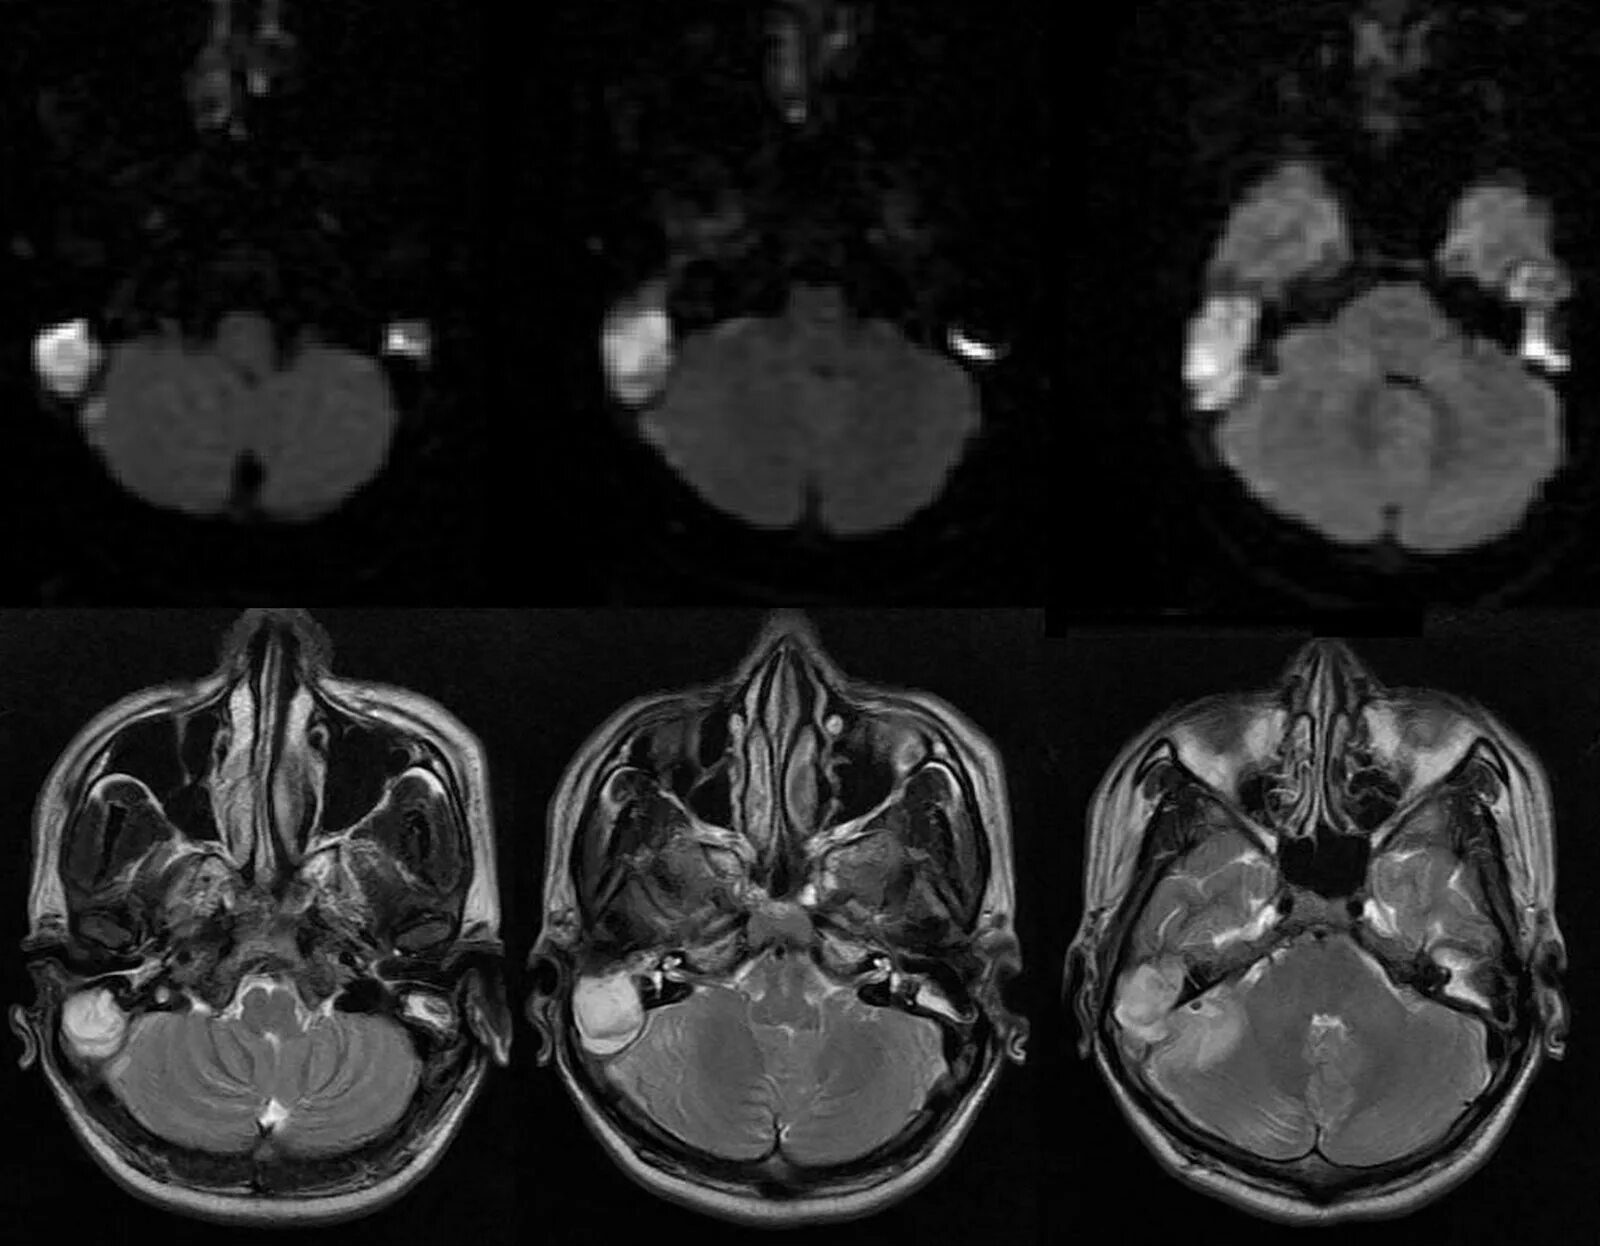

Мрт височных костей в режиме dwi